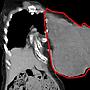

[新聞] 腫瘤撐爛左胸!醫掀開她衣驚見飛蛾竄出已回收

[ Gossiping ]68 留言, 推噓總分: +35

作者: Katsuyuki118 - 發表於 2018/06/23 12:27(7年前)

34Frayser: 盤絲大仙 五百年前?36.237.207.53 06/23 12:50